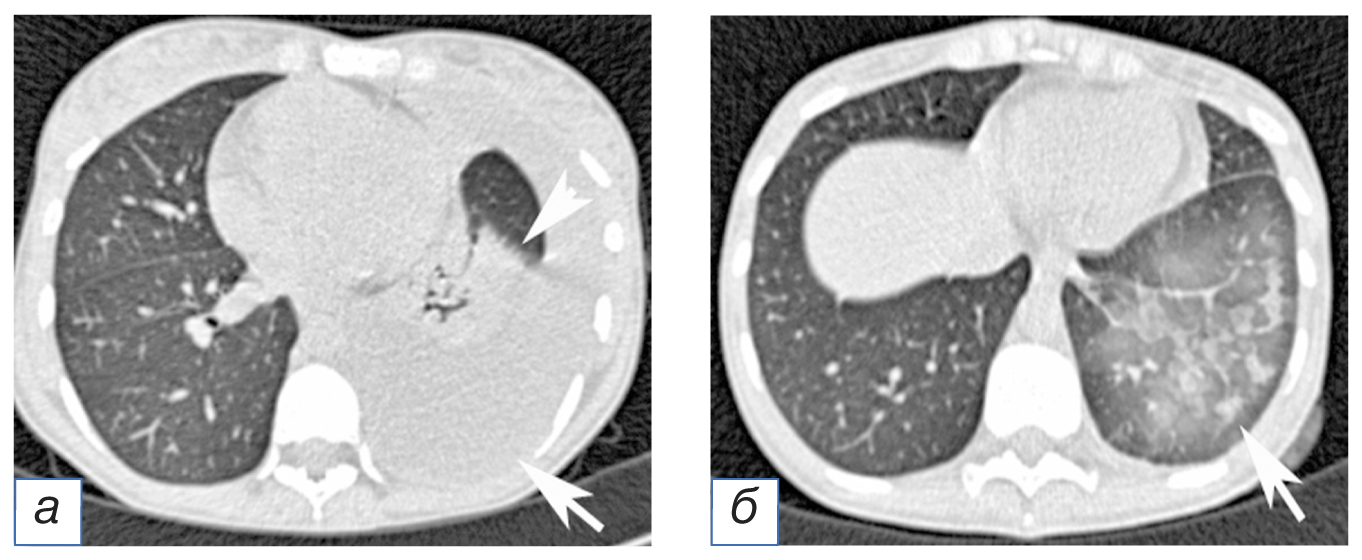

Лечение. Выполнена торакостомия с дренированием 1500 см3 воздуха. При контрольной компьютерной томографии определяются неполное расправление правого лёгкого, эмфизема мягких тканей грудной клетки (рис. 4, а). Пациентка хорошо перенесла процедуру, и симптомы патологического состояния уменьшились. На следующее утро у пациентки усилилась одышка, а сатурация кислорода (SpO2) снизилась до 86%. При повторной компьютерной томографии в левом лёгком определены множественные внутридольковые участки понижения прозрачности по типу матового стекла с гравитационными градиентами плотности (см. рис. 4, б). В совокупности с анамнезом данный симптом дал возможность прийти к заключению о развитии реэкспансивного отёка, так как у пациентки не было лихорадки и лейкоцитоза, характерных для пневмонии; отсутствовали признаки аспирации и перегрузки жидкостью, а также признаки почечной и сердечной недостаточности.

Рис. 4. Пациентка А., 53 года. Компьютерная томограмма грудной полости: а — скопление воздуха в правой плевральной полости (стрелка), эмфизема мягких тканей передней грудной стенки; б — скопление воздуха в правой плевральной полости (стрелка), эмфизема мягких тканей передней грудной стенки; снижение воздушности паренхимы левого лёгкого по типу матового стекла, обусловленное реэкспансивным отёком (головка стрелки).